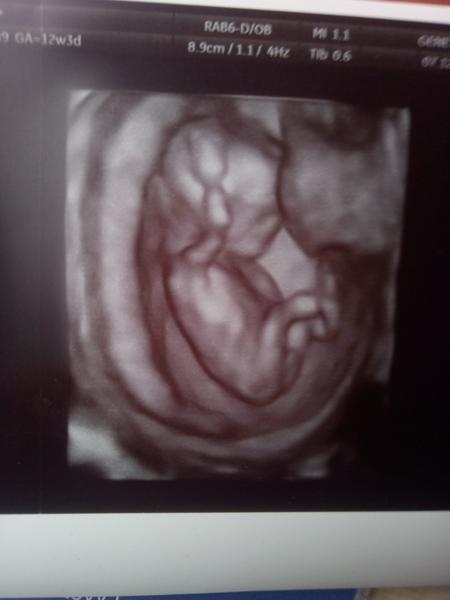

@krupka3 Tady je náš 14tt a dr přímo řešila hrbolek. Je vidět i na fotce 🙂 a myslím že ten 15tt nebude ještě jinak.